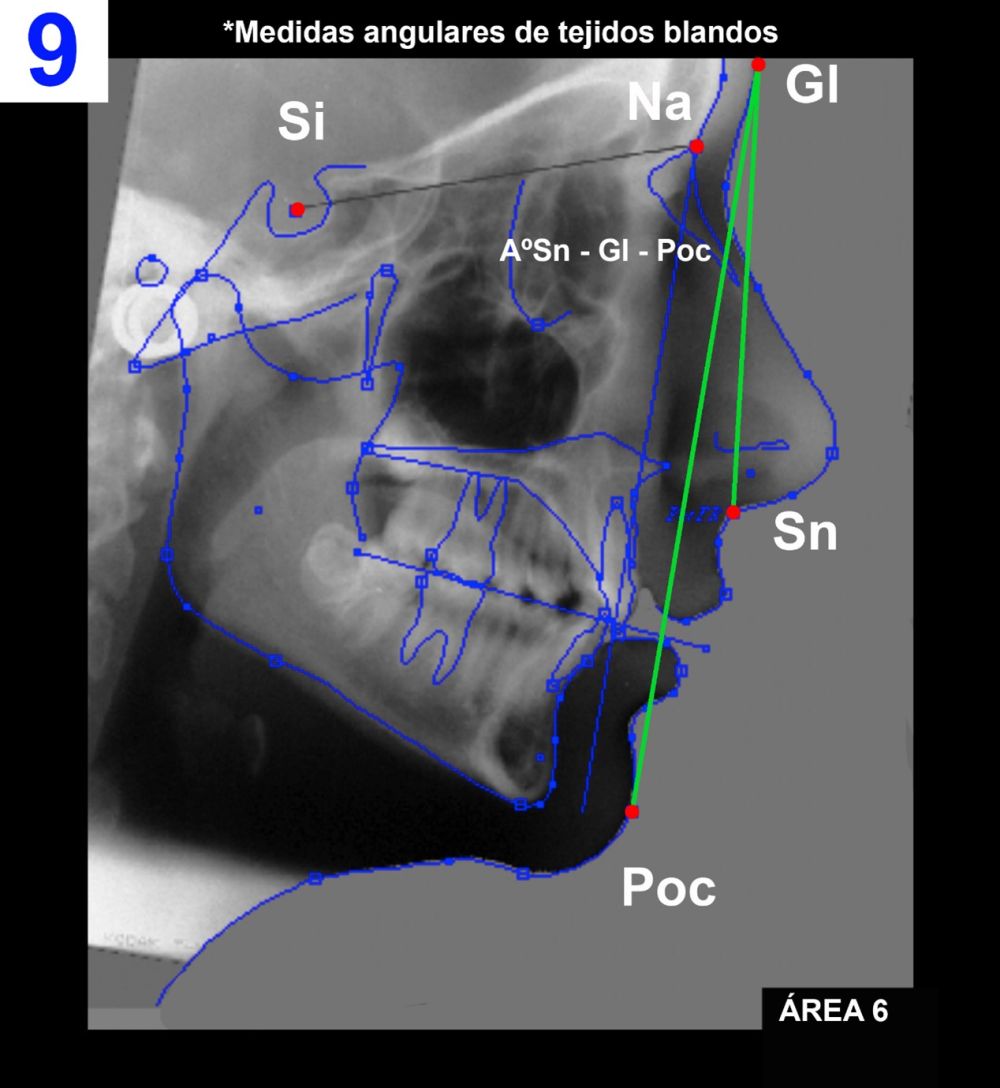

Área 6: Medidas angulares de tejidos blandos (Figura 9).

6.I) Sn – Gl – Poc.

Ángulo formado por los planos Gl – Poc y Gl – Sn.

Es también en el área 7 (Figura10 – medidas lineales de tejidos blandos), donde se evidencia que el tratamiento actúa estimulando el crecimiento mandibular, ya que en lo que respecta al crecimiento horizontal del maxilar a nivel de los tejidos blandos (distancia Gl – Sn) existe un escaso incremento, pero, por el contrario, es significativo el aumento del valor que determina el mismo crecimiento en la mandíbula (Gl – Poc).